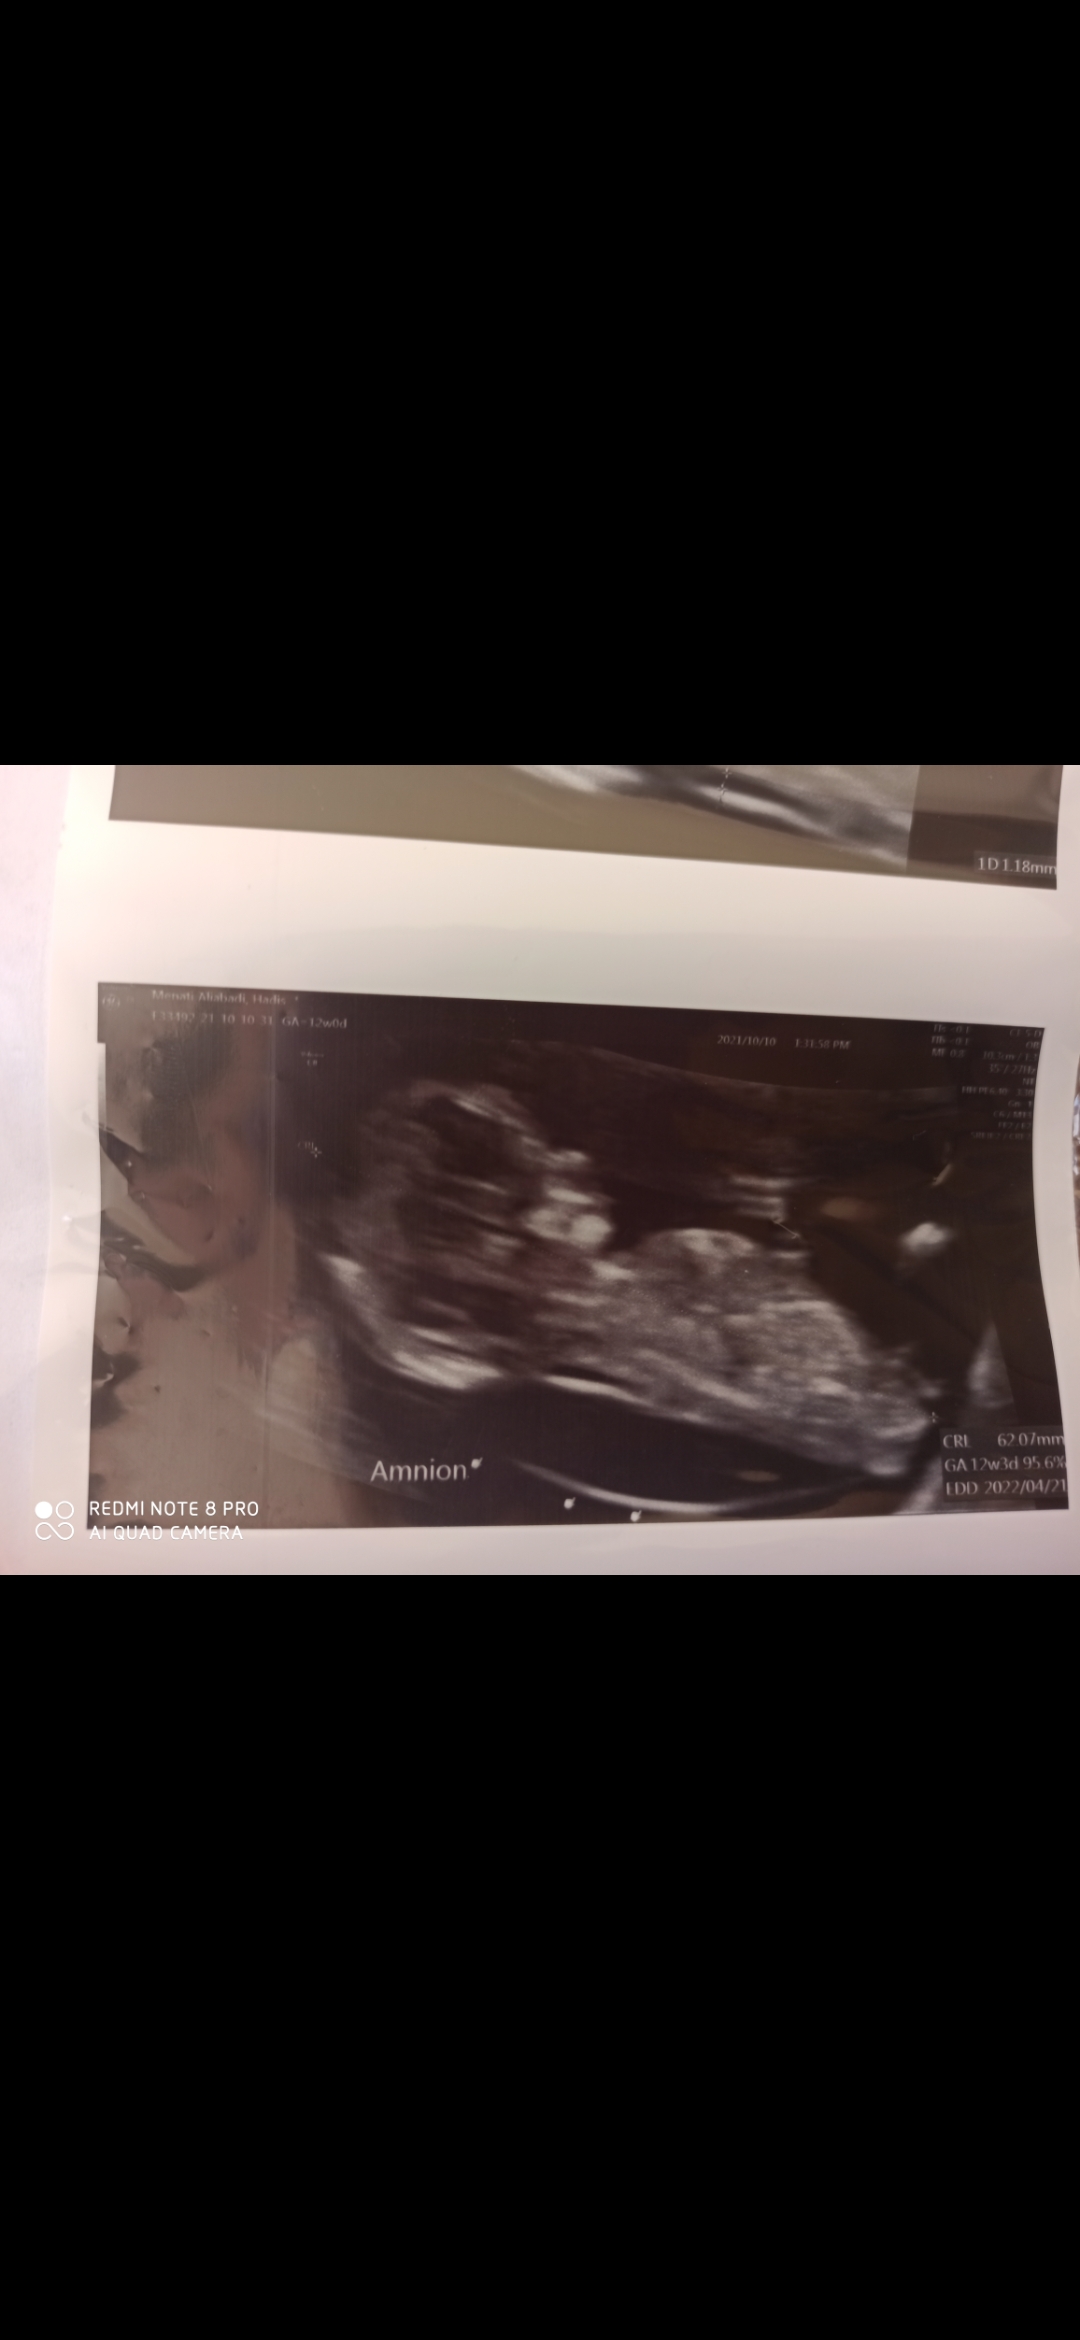

من عکس سونو nt , 12 هفتگیمو دارم , نمیدونی جنسیتش چیه ؟